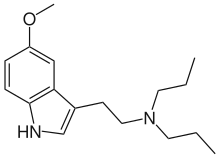

| DPT | artificial | H | CH2CH2CH3 | CH2CH2CH3 | N,N-dipropyltryptamine | 61-52-9 |